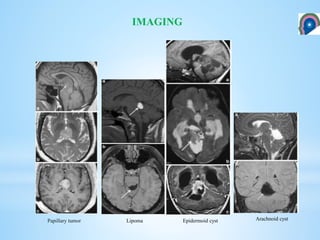

Lipoma Epidermoid cyst Arachnoid cystPapillary tumor

IMAGING Lipoma Epidermoid cystArachnoid cystPapillary tumor